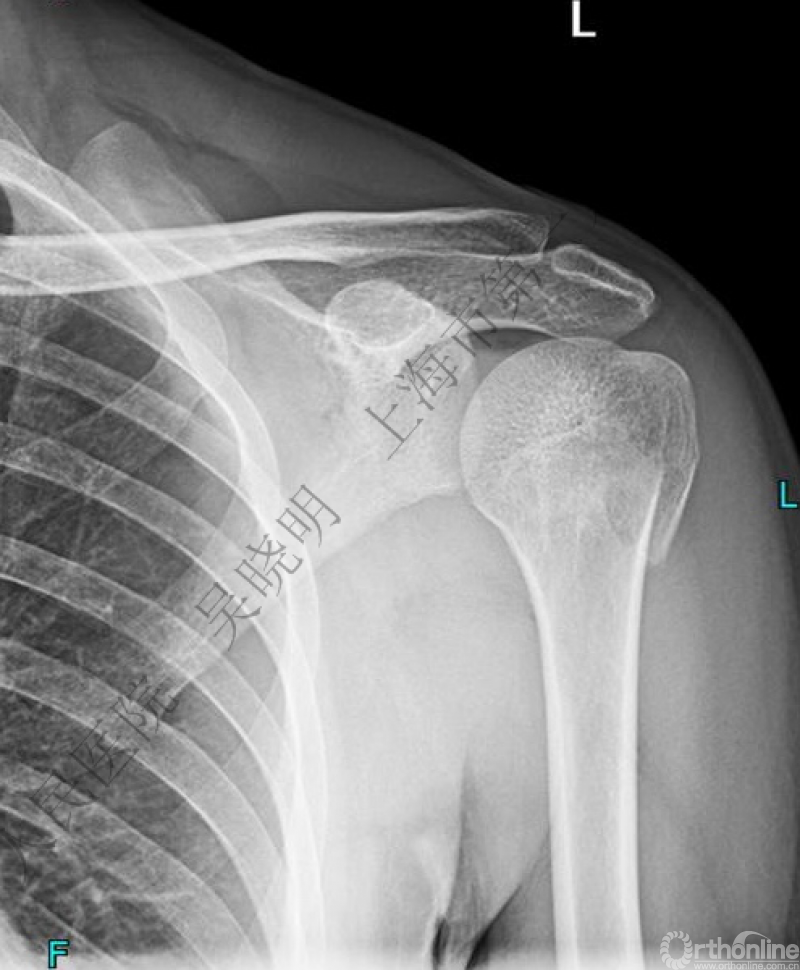

特别警惕伴肱骨头外翻合并大结节骨折的肩关节脱位

警惕:有无肱骨头外翻

肩关节前脱位伴大结节骨折:颈干角正常

无肱骨头外翻伴大结节骨折的老年性肩关节前脱位

Neer 分型:二部分大结节骨折脱位:手法复位

伴大结节骨折的老年性肩关节前脱位伴肱骨头外翻

肩关节前脱位合并大结节骨折&肱骨头外翻:外翻压缩型(Neer 分型)

对这型骨折进行手法复位会导致肱骨头和肱骨干之间的连续性消失。肱骨头和肱骨干之间连续性尚存,肱骨头前脱位(Robsion 3b)

警惕孤立性向下移位的大结节骨折

X线是孤立性向下移位的大结节,一定要小心,多伴有肱骨外科颈骨折